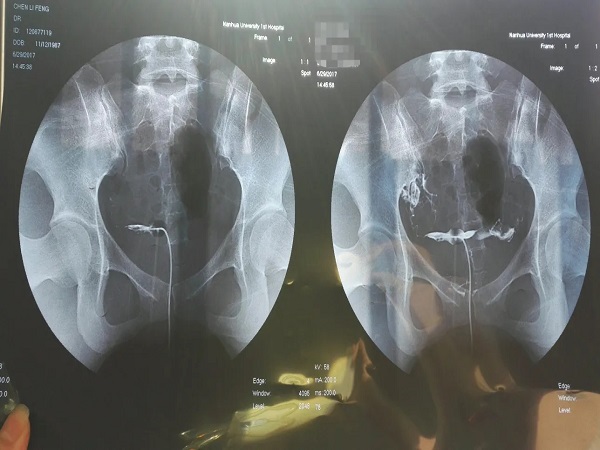

输卵管造影其实就是将造影剂从宫颈注射到女性的宫腔内,最后蔓延到输卵管位置,然后在放射线下面进行显影,就能够准确判断出女性是否存在输卵管不通畅的情况。如果存在异常的话,也能够找出异常的位置和病因,是非常有利于后期治疗的。